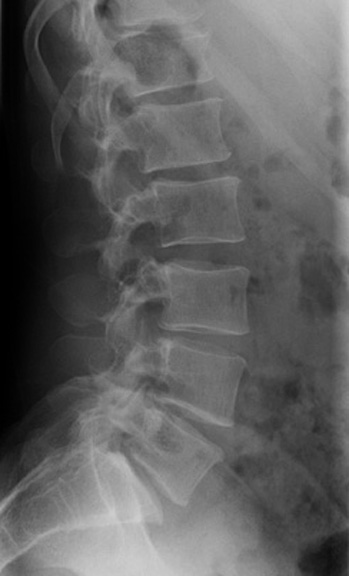

Number the lumbar vertebra. Click the image for labeling.